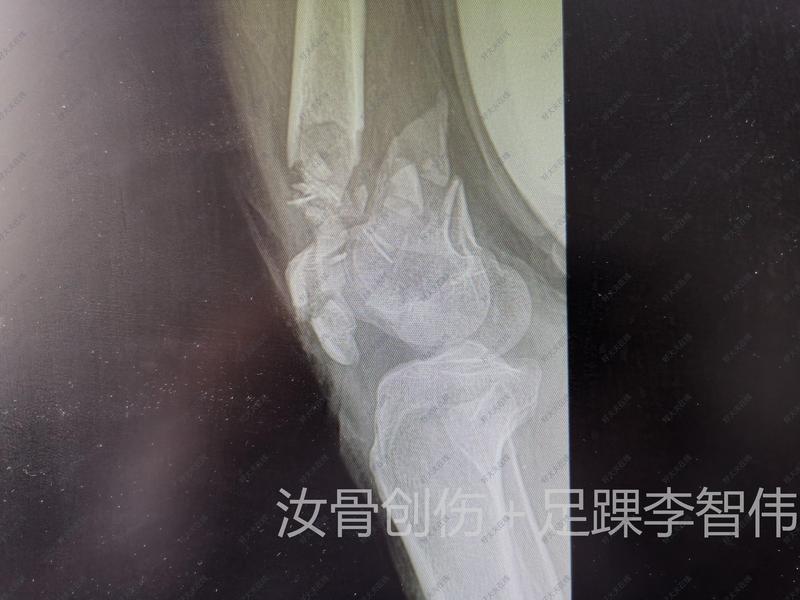

治療前 男,36歲,2米高墜落傷伴外翻損傷。致距骨頸骨折、距骨外側(cè)突撕脫性骨折(距腓前韌帶距骨附著處)。 治療中 踝關(guān)節(jié)外側(cè)切口,顯露距骨頸外側(cè)及距腓前韌帶距骨骨折塊。復(fù)位,克氏針臨時(shí)固定,無(wú)頭加壓釘+1枚掌骨板塑形后固定。 治療后 治療后7天 術(shù)中C臂透視位置可。 術(shù)后支具輔助下訓(xùn)練4周,4周后康復(fù)師指導(dǎo)下訓(xùn)練。 期待一個(gè)好的結(jié)果。